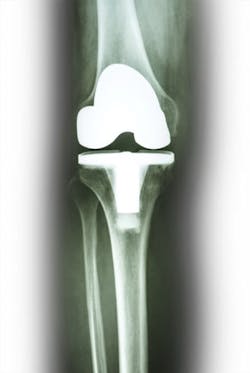

I chose this topic because-although over 1 million total joint replacement (TJR) surgeries are performed in the United States each year-there is controversy among orthopedic surgeons about the appropriate antibiotic premedication for dental patients who have undergone TJR.1,2 This controversy creates confusion among dental professionals regarding antibiotic premedication recommendations for their patients with TJR.

Contributing to the confusion is the fact there is no well-documented evidence that infected TJRs are caused by bacterial species specific to a dental procedure.3 Also, the AAOS has changed the premedication guidelines three times since 2003. These changes are not only confusing to patients, but can be frustrating to dental care providers who attempt to answer questions regarding the changes. I've had a patient say to me, "Can't you guys just make up your mind?" Explaining to them that science is not stagnant does not always satisfy their queries.